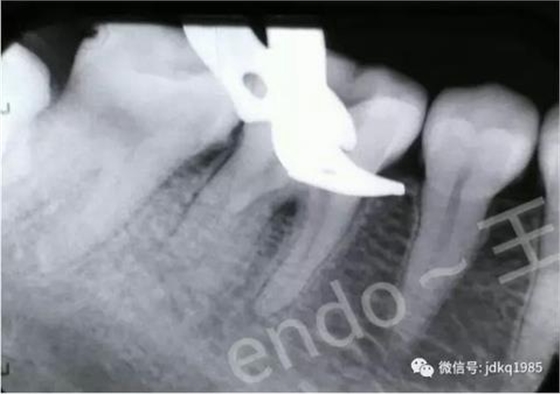

取出的斷針

術(shù)后X線片,確認(rèn)近中根管內(nèi)分離器械已成功清理